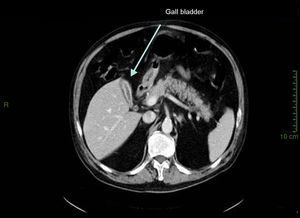

Case presentationIn October 2010 a 74-year-old Caucasian male was admitted because of fever, anuria and mialgia lasting for 2 days. He had no history of renal disease and reported previous normal values of renal function. A month earlier he had travelled to a region of Southern Italy. Physical examination showed normal blood pressure, dyspnoea and jaundice without other dermatological findings; the patient was anuric with 2+pedal oedema. Initial laboratory work-up indicated a total leucocyte (WBC) count of 11,300/μL (neutrophils 88.3%, lymphocytes 11%, eosinophils 0.7%), a haemoglobin level of 9.7g/dL, platelets count of 13,000/μL, serum creatinine 5.25mg/dL, blood urea nitrogen (BUN) 67g/dL, total protein 6.7g/dL, albumin 2.9g/dL, serum sodium 130mEq/L, serum potassium 3.3mEq/L, serum calcium 8.4mg/dL; total cholesterol 254mg/dL; LDL cholesterol 48mg/dL; HDL cholesterol 22mg/dL, procalcitonin 45.71ng/mL, normal value (n.v.)<0.09, Reactive C Protein 22.70mg/dL, n.v.<0.30, ferritin 1300μg/L. Complement C3 and C4, Immunoglobulin G, A and M, kappa and lambda light chains, clotting profile, AST and ALT levels were in the normal range. Total and direct bilirubin values were respectively 4.3 and 2.1mg/dL. Immunological (anti-neutrophil cytoplasm antibodies, anti-nuclear antibodies, anti-double stranded DNA antibodies, anti-extractable nuclear antigen antibodies, anti-phospholipids antibodies, rheumatoid factor) tests were unremarkable. A chest X-ray showed multiple bilateral ground-glass opacities (Fig. 1). A thoracic CT-scan revealed multiple bilateral consolidations and bilateral pleural effusion (Fig. 2). There was to electrocardiogram evidence of normal sinus rhythm and transthoracic echocardiography demonstrated no wall motion abnormality. An abdominal ultrasonography and a CT-scan revealed no abnormalities of liver, gallbladder, kidneys, spleen and pancreas. At the same time of antibiotic, platelet transfusion and diuretic therapy we started continuous venovenous haemofiltration (CVVHF) with weight loss and rapid regression of dyspnoea. Two days after admission the patient showed melena. Subsequent laboratory tests indicated: normal oncologic screening; no signs of haemolytic anaemia; red blood cells and WBC in urinary sediment; a total of 475mg of protein was excreted during a 24-h urine collection; blood cultures examination, tuberculin reaction and HBV, HCV, CMV, EBV, Adenovirus, Chlamydia Pneumoniae and Mycoplasma Pneumoniae screening were negative. During hospitalization we observed a worsening of liver function (total and direct bilirubin respectively 17.30 and 10.50mg/dL, gammaGT 267IU/L, n.v. 7–50, LDH 1027IU/L, n.v. 266–530, AST: 67IU/L, n.v. 10–42, ALT 96IU/L, n.v. 10–45) and inflammation parameters (WBC count 25,250/μL, neutrophils 76.6%, ferritin 4200μg/dL). An abdomen CT-scan highlighted greatly thickened gallbladder and bile duct walls with contrast enhancement, peritoneal effusion and swelling of the visceral adipose tissue (Fig. 3). We performed the Leptospira IgM test (enzyme immunoassay) with positive result. After platelets and erythrocytes transfusions and omeprazole therapy, we started 3g/day ceftazidime and 50mg/day prednisone therapy with a progressive improvement in renal function and general conditions; after 10 days of admission we stopped CVVHF. A thoracic CT scan showed resolution of previously observed lesions. The patient was discharged on day 18. Final laboratory parameters were: creatinine: 0.93mg/dL, BUN: 26mg/dL, total and direct bilirubin respectively 6.50 and 3.40mg/dL, AST: 47IU/L, ALT: 84IU/L, gammaGT: 137IU/L, LDH: 609IU/L, WBC 3420/μL, Hb: 8.3g/dL, and PLT: 262,000/μL.